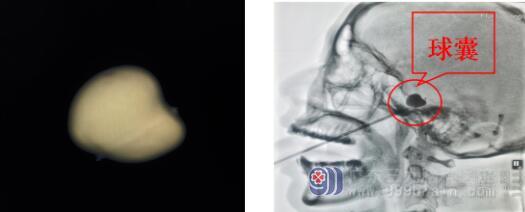

据李医生解释,三叉神经痛是最常见的脑神经疾病,多为中老年人群,以一侧面部三叉神经分布区内反复发作的阵发性剧烈痛为主要表现。号称“天下第一痛”的三叉神经痛,是疼痛界的冠军!三叉神经痛分为原发性三叉神经痛和继发性三叉神经痛。原发性三叉神经痛病因是颅内小血管压迫三叉神经根所致;继发性三叉神经痛往往是因为颅内病变所致。患者黄女士属于继发性三叉神经痛,原因是颅内肿瘤(胆脂瘤)压迫三叉神经根所致。大部分患者切除肿瘤后疼痛可缓解,部分患者疼痛还可能复发,黄女士就属于这种情况。对于复发的继发性三叉神经痛,如果考虑肿瘤复发导致,可再次行肿瘤切除,对于未发现肿瘤复发的患者,可采取经皮穿刺球囊压迫术。

在排除手术禁忌症、完善术前准备后,神经外十科欧阳辉主任带领的医生团队在全麻下为黄女士实施了“右侧三叉神经半月节微球囊压迫术” 。